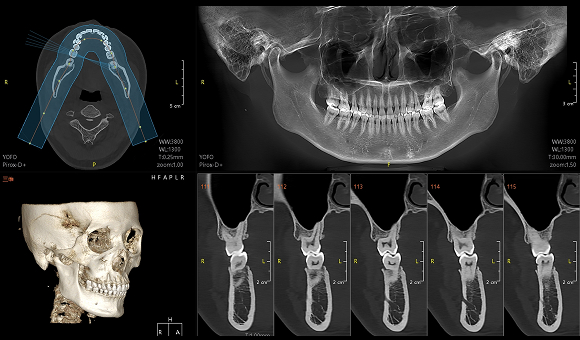

只需一次单圈扫描即可获得CT、3D全景和3D正/侧位影像,并能同时生成3D TMJ视图

提高诊疗效率,避免过度检查,减少患者所受的辐射

• CT

CT

• 3D全景

3D全景

• 3D 正侧位

3D 正侧位

• 3D TMJ视图

3D TMJ视图

拍一次就好

一次拍摄同时获得三种影像

扫描快、摆位快、出图快

拍完2.6s出图